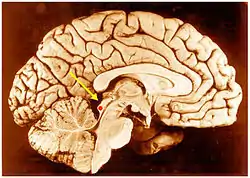

![]() Inferior colliculus (red dot) in human brain, sagittal section. | |